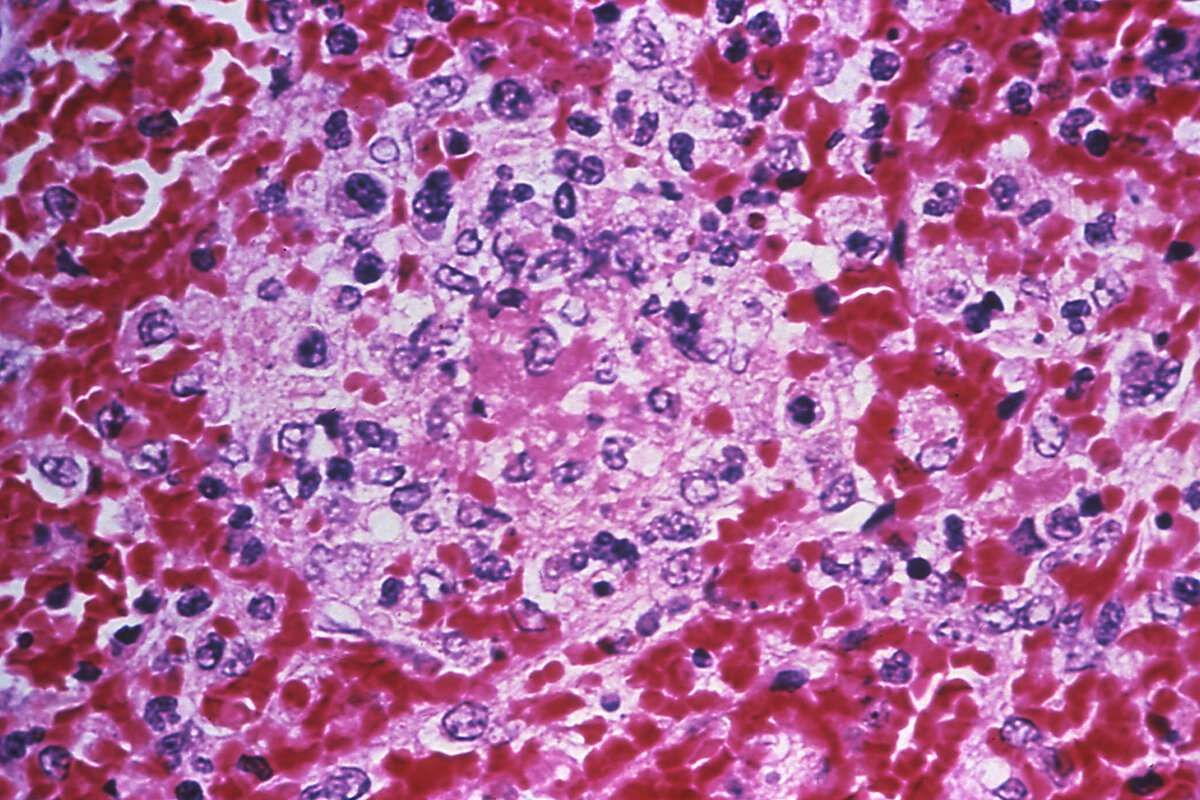

Микрофотография гистопатологических изменений в ткани селезенки в случае заражения чумой человека Фото: CDC/Dr. Marshall Fox / Smith Collection / Gado / Getty Images

Основной удар приходится на лимфатическую систему, в результате чего в подмышках и паху зараженного возникают увеличенные лимфатические узлы размером с куриное яйцо — бубоны. Помимо появления бубонов, среди симптомов чумы — повышенная температура, головная боль, слабость и тошнота. Иногда бубонная чума провоцирует пневмонию — тогда инфекция может передаваться воздушно-капельным путем. Без своевременного лечения антибиотиками воспаленные лимфоузлы превращаются в открытые гноящиеся раны.